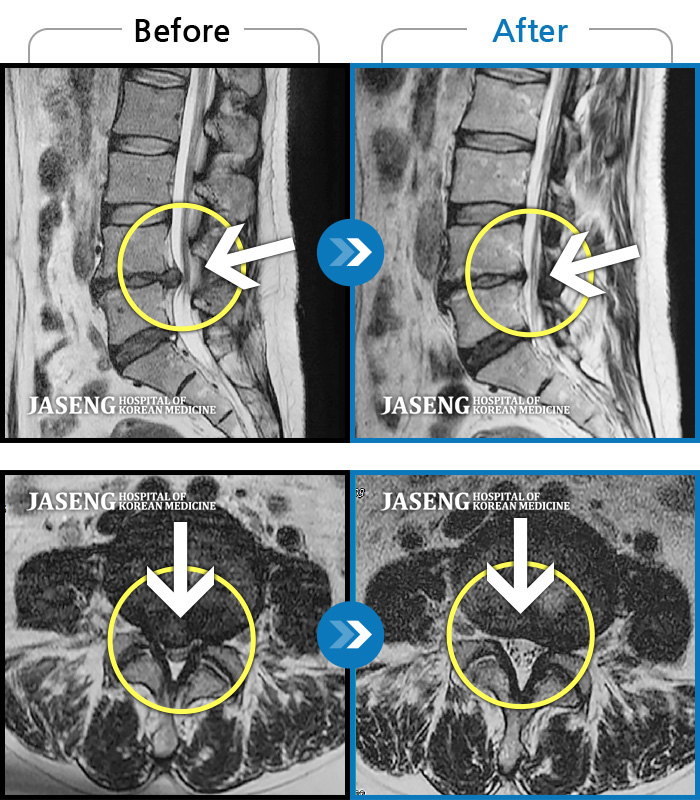

허리디스크

인천 · 조남훈 원장

좌측 허벅지와 종아리가 찌릿하고 묵직한 통증이 있어요.

촬영시기

2025.03.18 ~ 2025.07.22

2025.08.01